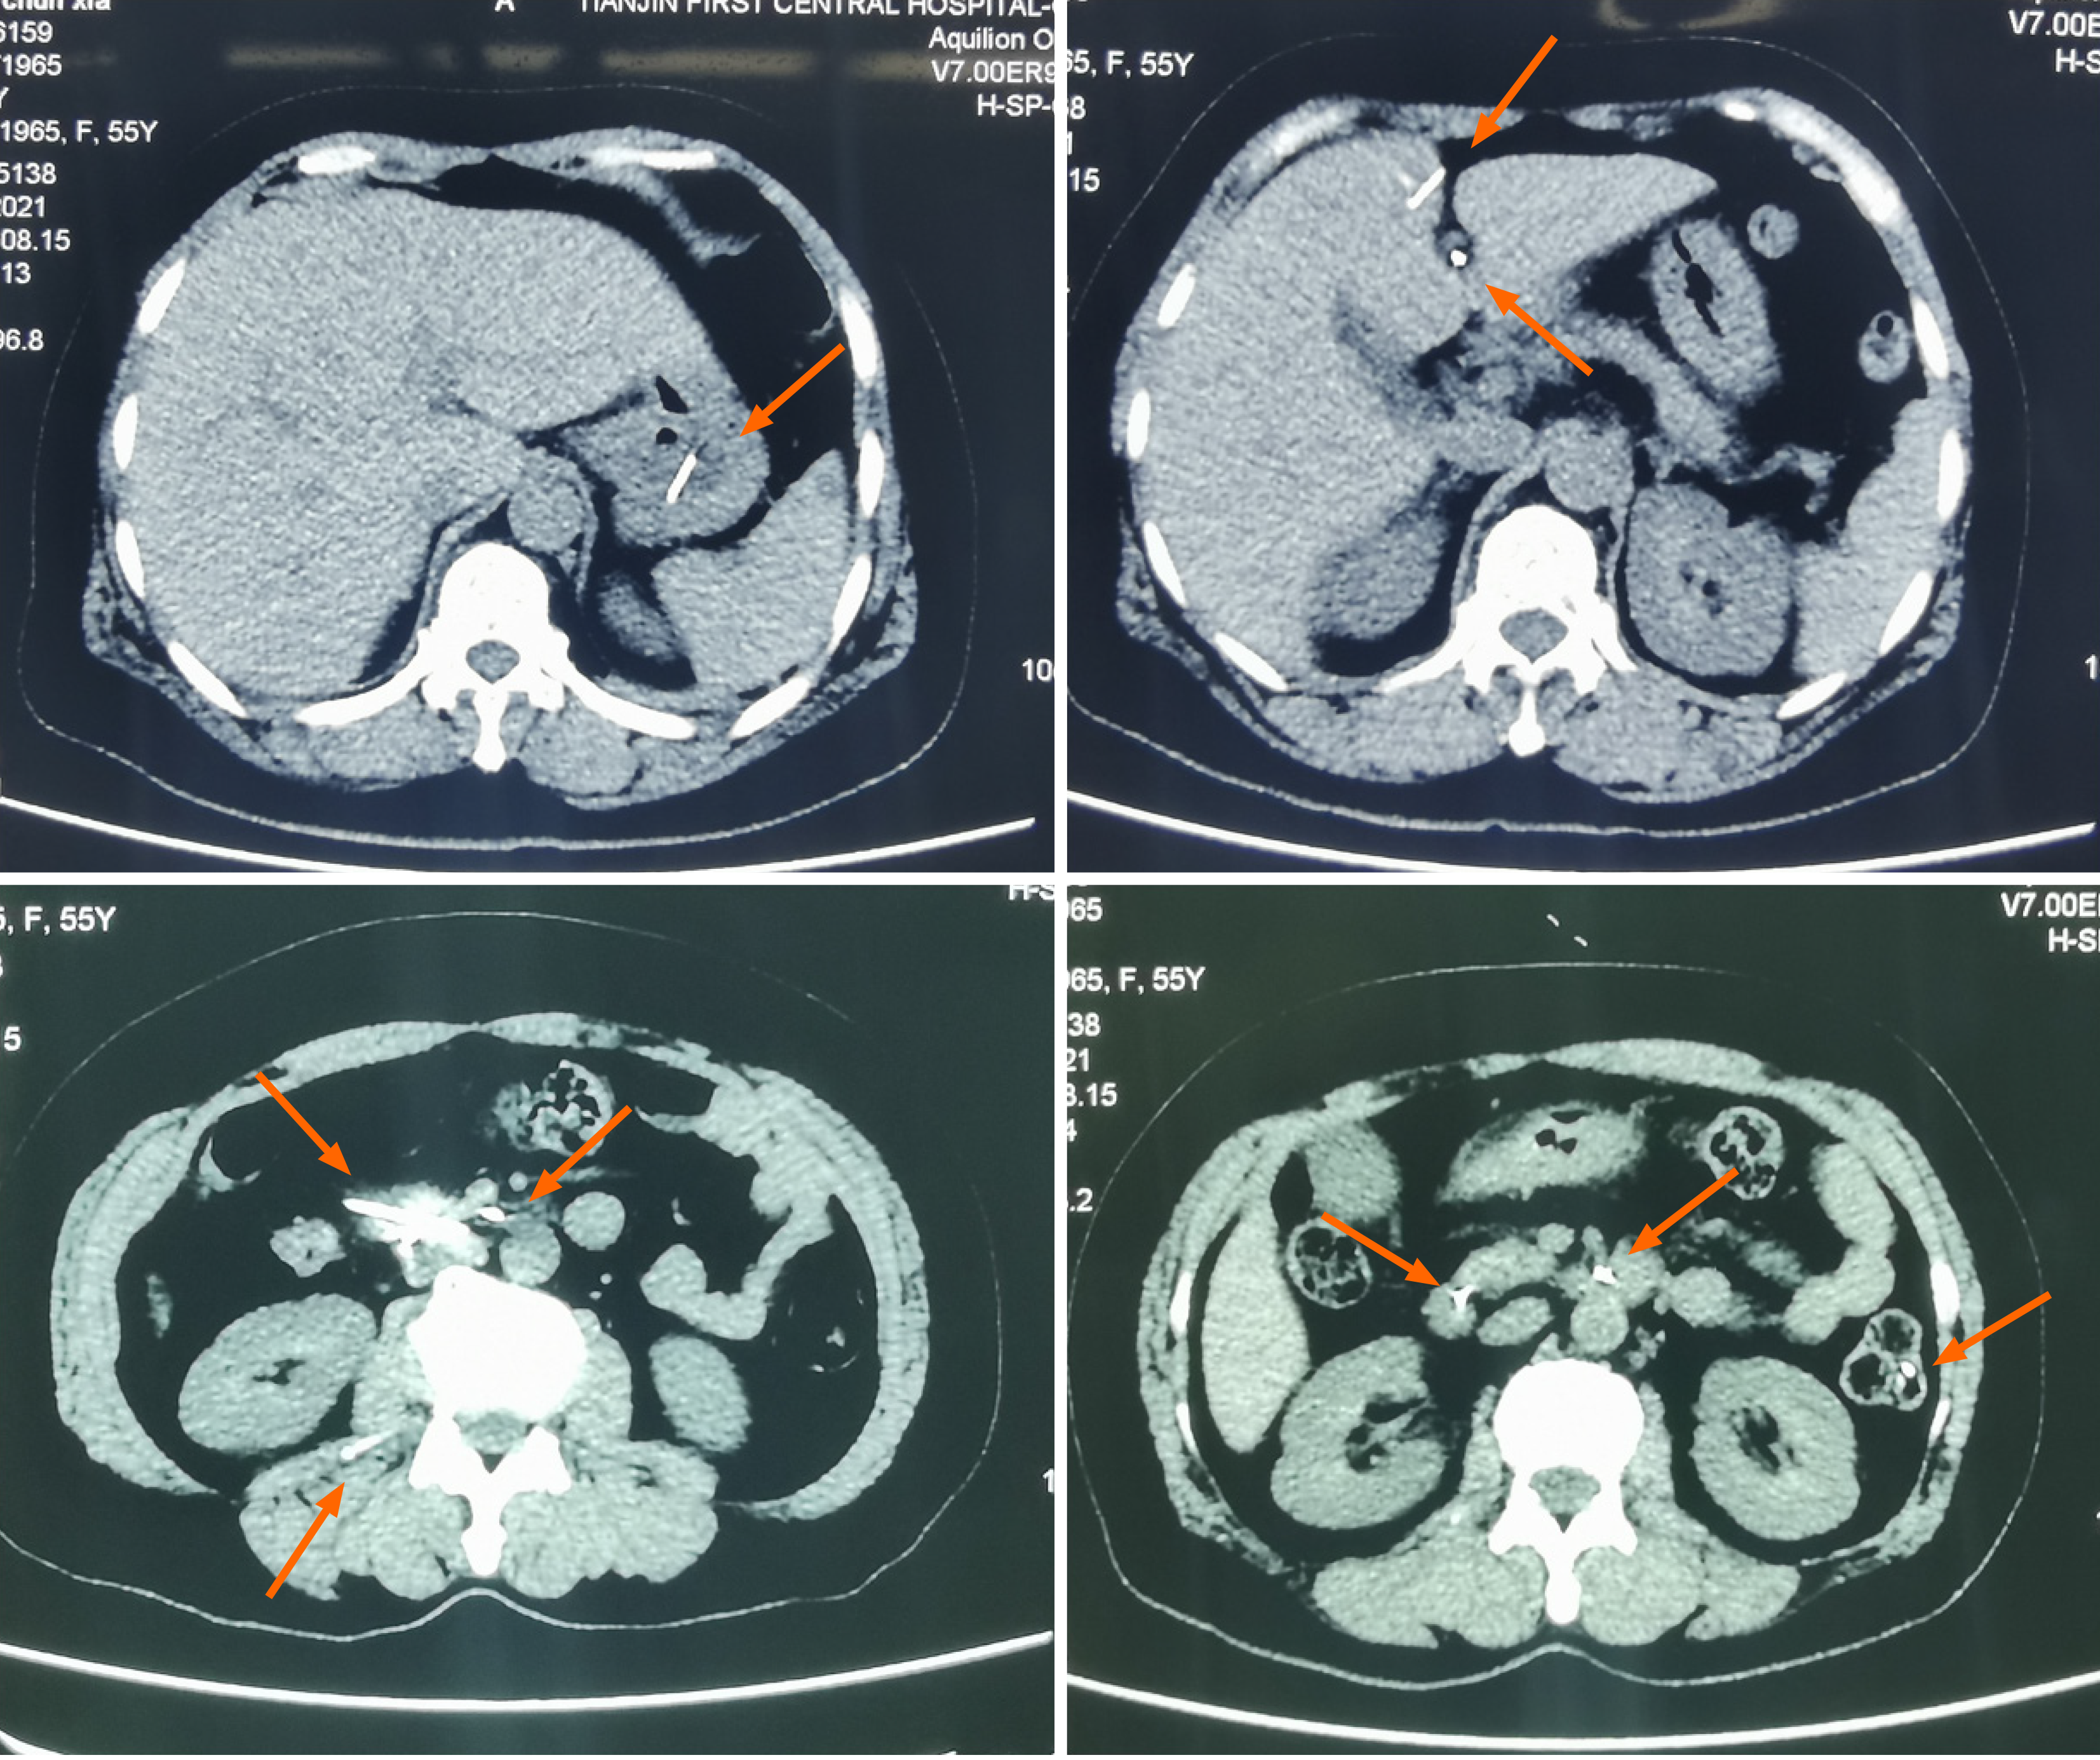

Figure 2 Axial computed tomography imaging of metallic foreign body distribution in the abdominal cavity (orange arrows).